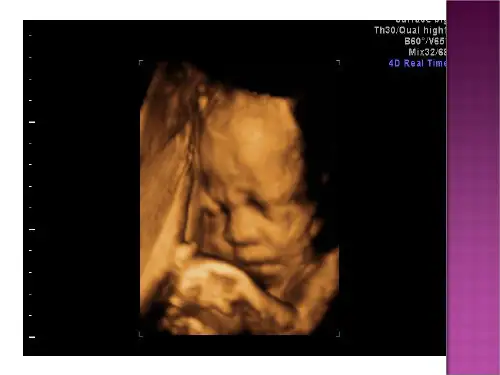

超声检查已经发展到了Ⅲ级产前超声检查,能够提供更清晰、更全面的胎儿图像,帮助医生做出更准确的诊断。

该指南还提到了一些常用的超声检查技术,如超声心动图、三维和四维超声等。